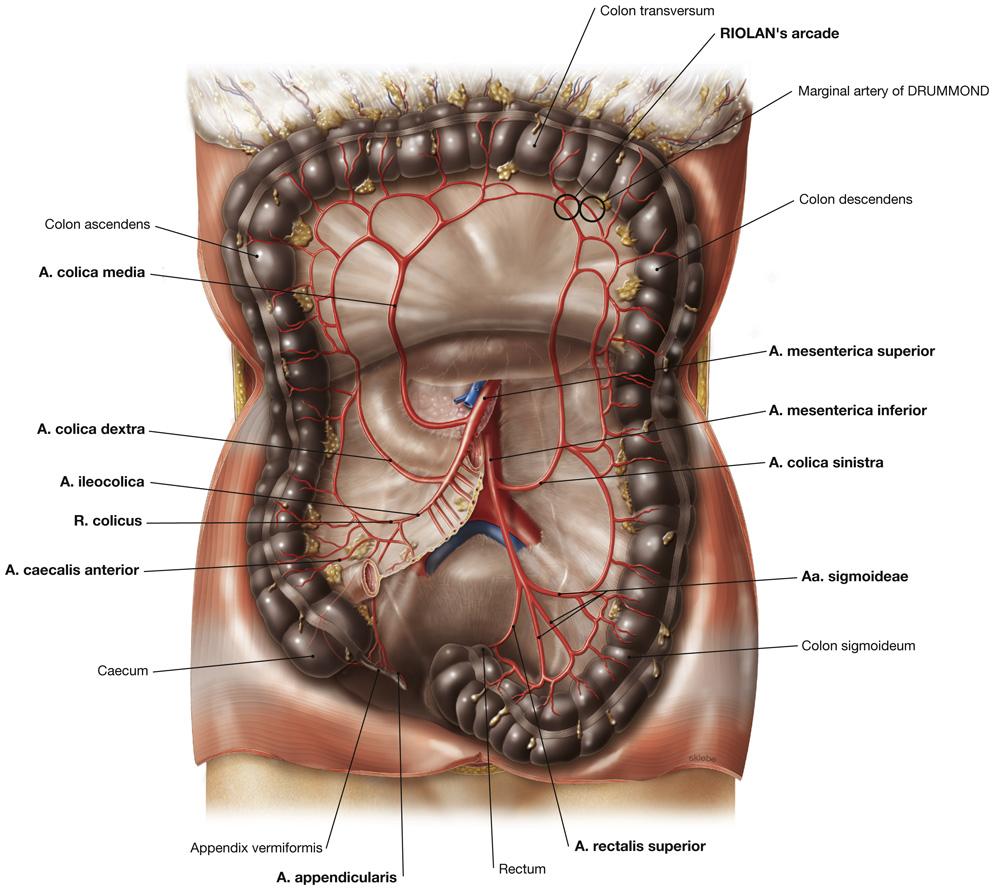

Fig 3.24: a. mesenterica inferior (AMI)

|